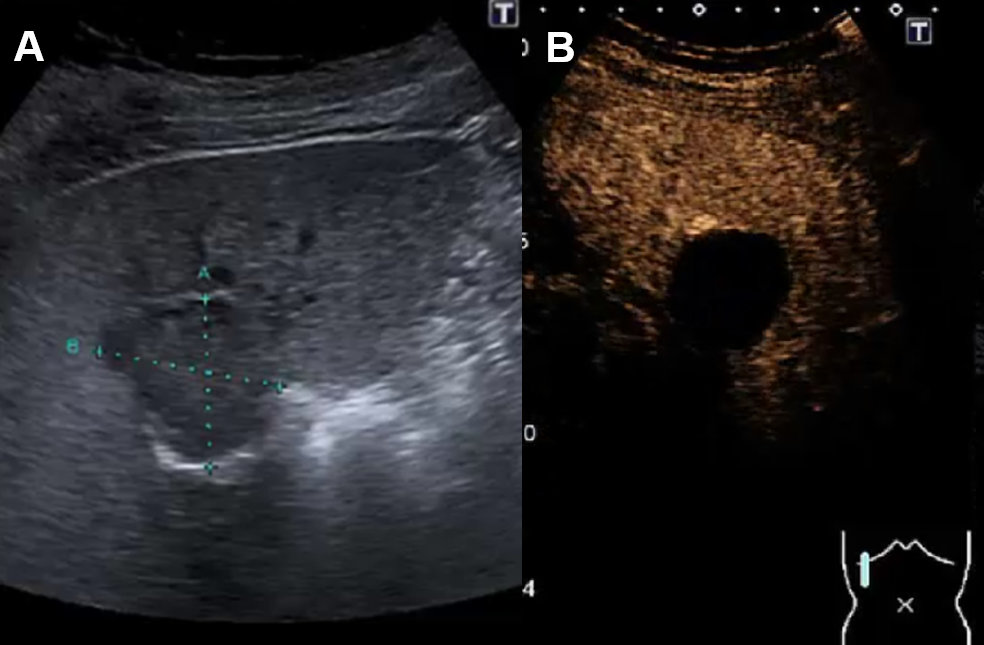

Conventional ultrasound is the first imaging modality to demonstrate fluid-containing lesion with smooth thin wall with a sensitivity and specificity of 90% [2, 9]. Simple liver cysts are non-enhancing on CEUS [3]. Septation, mural irregularity/mural nodularity or echoic internal material define a complex liver cyst needing further investigation. Vascular perfusion with septa or solid enhancing noduli of the liver cyst can be demonstrate or excluded by CEUS (figure 5). Alternatively, CT or MRI are very sensitive imaging modalities in this scenario.

Figure 5Liver cyst on ultrasound and CEUS. A Ultrasound with cystic lesion with echogenic content. B CEUS without contrast-enhancement demasking a complex hepatic cyst.